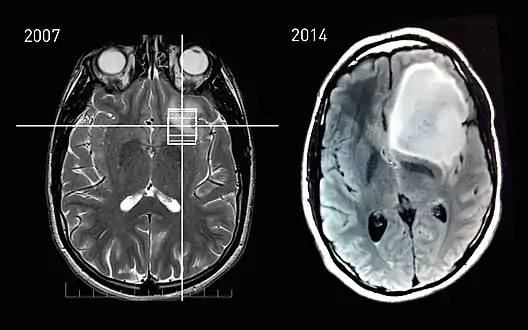

MRI scans of an astrocytoma patient, showing tumor progression over the course of seven years